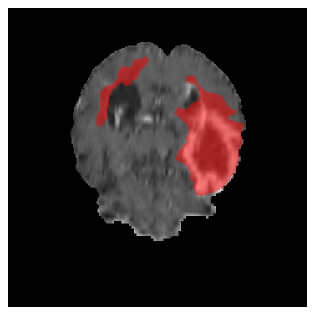

Appendix A Qualitative results

Figures 4 and 5 present the segmentation results for a patient from the BRATS dataset, visualized on a randomly selected slice. Figure 4 illustrates how tumor segmentation evolves over multiple episodes in S1 across different approaches including cumulative, naive, our approach, and the best buffer-free strategy (SI, =2). The cumulative approach, which trains on all encountered datasets together, maintains segmentation consistency across episodes but introduces significant amounts of false positives, particularly in the upper left area of the brain images. These misclassifications highlight its inability to generalize well across datasets despite access to all previous data. The naive approach, which learns sequentially without any continual learning strategy, suffers from severe catastrophic forgetting. While it initially segments well, performance deteriorates over episodes, leading to a near-complete loss of segmentation capability by the final episode. The SI (=2) approach, a regularization-based buffer-free CL strategy, performs reasonably well in early episodes but shows a significant performance decline over time. By the last episode, much of the tumor was no longer segmented, indicating difficulty in retaining prior knowledge. In contrast, our proposed approach initially produces more false positives but progressively refines its segmentation. By the final episode, it accurately retains the tumor region while minimizing misclassifications, demonstrating strong knowledge retention and adaptability across episodes. This suggests that our approach effectively mitigates catastrophic forgetting while maintaining segmentation performance over sequential learning.